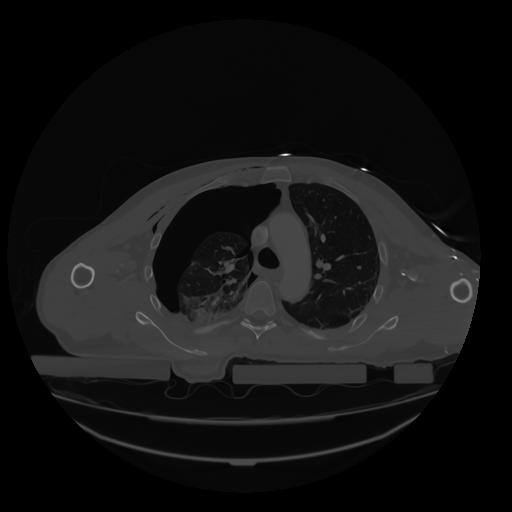

28 CUERPO,CE,Vol,2.0,CUERPO,,